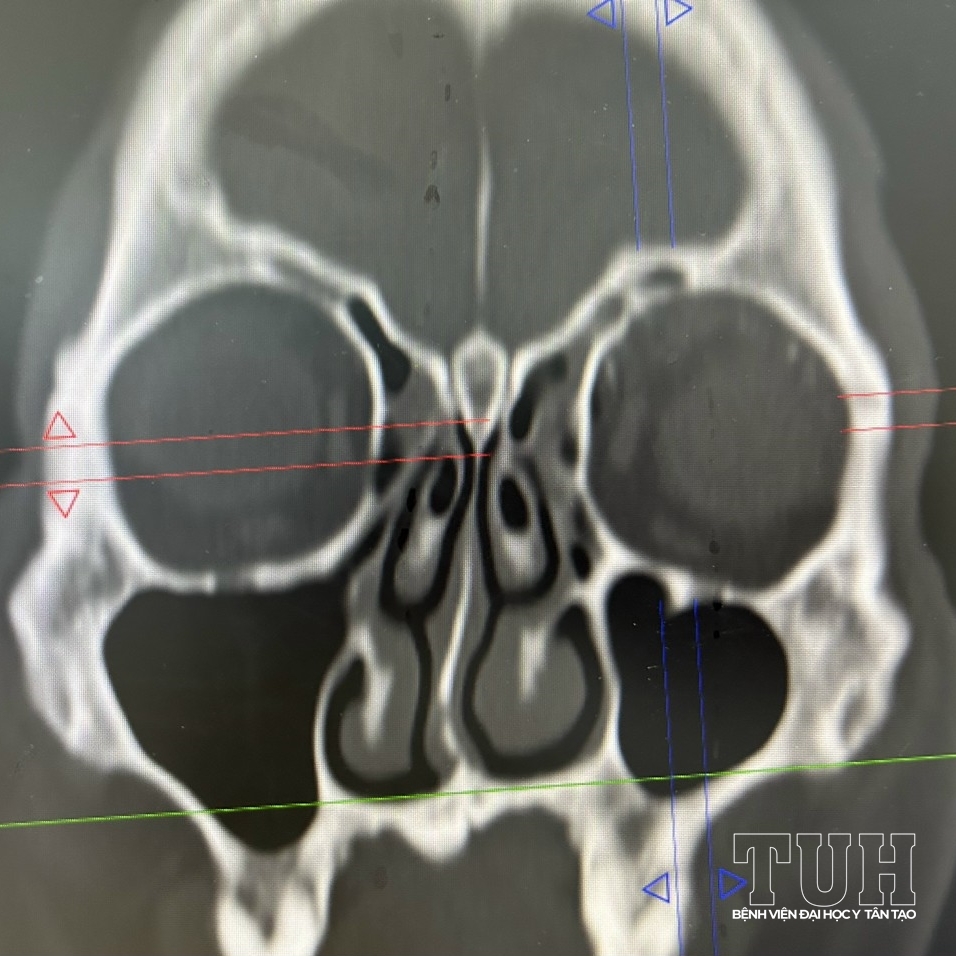

Ngày 26/4, Bệnh viện Đại học Y Tân Tạo cấp cứu nan nhân V.H.T trong tình trạng vỡ hở thành trước xoang trán do tai nạn lao động.

Sau khi đánh giá tổn thương phối hợp hội chẩn liên khoa, bệnh nhân được đánh giá thành sau và trần sàng nguyên vẹn, khớp mũi trán không gãy, không đặt dẫn lưu ngách trán vì không ảnh hưởng đến ống mũi trán.